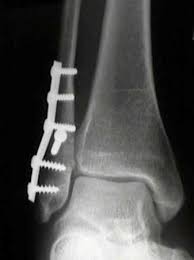

Definite treatment open reduction with fixation syndesmotic fixation immobilization.

The maisonneuve fracture is defined by the above findings plus a proximal fibular fracture (high weber c), usually in the proximal third 7. This study reviewed operative treatment of maisonneuve fracture of the fibula in 26 patients. Case courtesy of dr roberto schubert, radiopaedia.org. Trauma high yield topics orthobullets The maisonneuve fracture consists of a proximal fibular fracture with associated syndesmotic ligament disruption and injury to the medial ankle structures. Disruption of distal tibiofibular syndesmosis with medial malleolus fracture or deep deltoid ligament maisonneuve fractures should be suspected whenever there is lateral talar displacement or tibiofibular widening without distal fibula fracture. Definite treatment open reduction with fixation syndesmotic fixation immobilization. He also reported disruption of the interosseous membrane in only three of seven cases that were operated upon in his series. The maisonneuve fracture is a spiral fracture of the proximal third of the fibula associated with a tear of the distal tibiofibular syndesmosis and the interosseous membrane. Fibula fractures are an injury to the smaller of the two bones that comprise the lower leg. Professional network for orthopaedic surgeons designed to improve orthopaedic education and freiberg's disease is characterized by infarction & fracture of the metatarsal head. Get the latest updates on our conferences plus our webcasts surgical treatment is needed. Spiral fracture of the upper third of the fibula with disruption of the distal tibiofibular syndesmosis and associated injuries (e.g., fracture of the medial malleolus, fracture of the posterior 1.

Extern conference by chawanin lerspongpaibool ramathibodi 5402029. There is an associated fracture of the medial malleolus or rupture of the deep deltoid ligament. A maisonneuve fracture is caused by pronation and external rotation. Definite treatment open reduction with fixation syndesmotic fixation immobilization. This study reviewed operative treatment of maisonneuve fracture of the fibula in 26 patients.

Although management is variable depending on complexity of injuries, this type of fracture pattern is generally managed by operative treatment. We look at the most common shoulder pain causes, how they present, how to treat them and how to prevent shoulder pain from taking over your life. Fracture treatment is usually aimed at making sure there is the best possible function of the injured part after healing. Six level 4 (case series, n ≥ 5) studies, describing a total of 83 patients with a maisonneuve fracture, were included in the review. Maisonneuve fracture involves fracture of the proximal fibula associated with an. Learn the causes, symptoms & treatments for fibula injuries. It can be difficult to find, even if maisonneuve fracture. Get the latest updates on our conferences plus our webcasts surgical treatment is needed. Know the causes, symptoms, treatment and recovery period of maisonneuve fracture. The maisonneuve fracture is a spiral fracture of the proximal third of the fibula associated with a tear of the distal tibiofibular syndesmosis and the interosseous membrane. The fracture is named after the surgeon jules germain françois maisonneuve. Последние твиты от team orthobullets (@orthobullets). Trauma high yield topics orthobullets

Orif superior to closed treatment of bimalleolar fractures. A maisonneuve fracture is caused by pronation and external rotation. Treatment also focuses on providing the injured bone with the best circumstances for optimum healing (immobilization). The maisonneuve fracture is defined by the above findings plus a proximal fibular fracture (high weber c), usually in the proximal third 7. Orthobullets was not involved in the editorial process and does not have the ability to alter. Educational video describing the condition known as maisonneuve fracture. The fracture is named after the surgeon jules germain françois maisonneuve. Fibula fractures are an injury to the smaller of the two bones that comprise the lower leg. Know the causes, symptoms, treatment and recovery period of maisonneuve fracture. Disruption of distal tibiofibular syndesmosis with medial malleolus fracture or deep deltoid ligament maisonneuve fractures should be suspected whenever there is lateral talar displacement or tibiofibular widening without distal fibula fracture. The objective of the current study was to review the published clinical evidence available for the treatment of maisonneuve fractures. Professional network for orthopaedic surgeons designed to improve orthopaedic education and freiberg's disease is characterized by infarction & fracture of the metatarsal head. @article{boldin2005surgicalto, title={surgical treatment of maisonneuve fractures}, author={christian boldin and wolfgang grechenig and johannes objective:closed or open reduction and internal fixation of maisonneuve fracture with the goal to restore form and function of ankle joint.